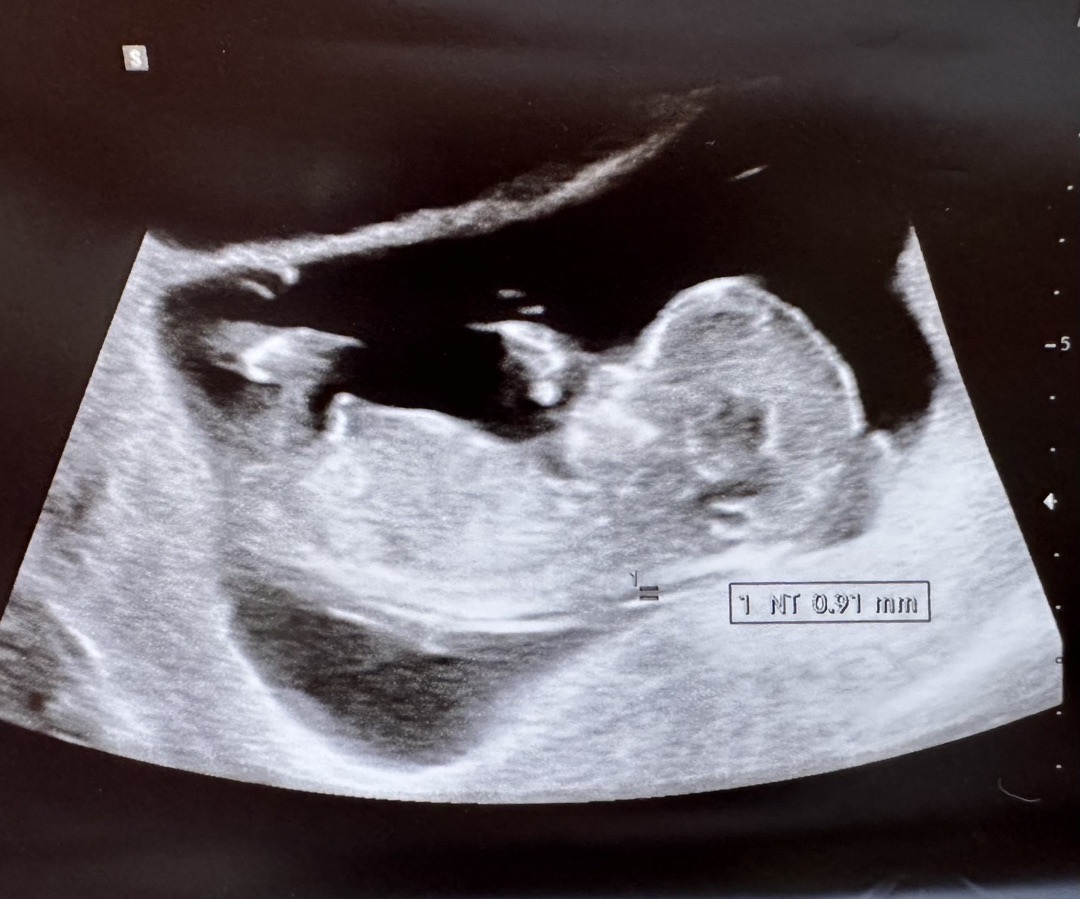

12주 아들일까요 딸일까요? 🍑🌶️

마미톡이 안되는 병원이라 ㅜㅜ 금요일에 가야 정확할거같긴 한데 그전에 궁금해서 올려봐용